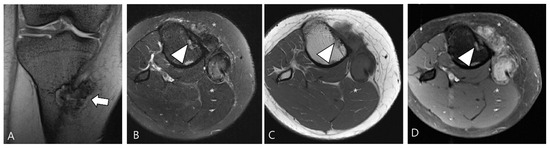

3.2. Differential Diagnoses of Extra-Articular D-TSGCT

3.2.1. Fibroma of the Tendon Sheath (FTS)

3.2.2. Extra-Abdominal Desmoid-Type Fibromatosis (DF)

3.2.3. Tophaceous Gout